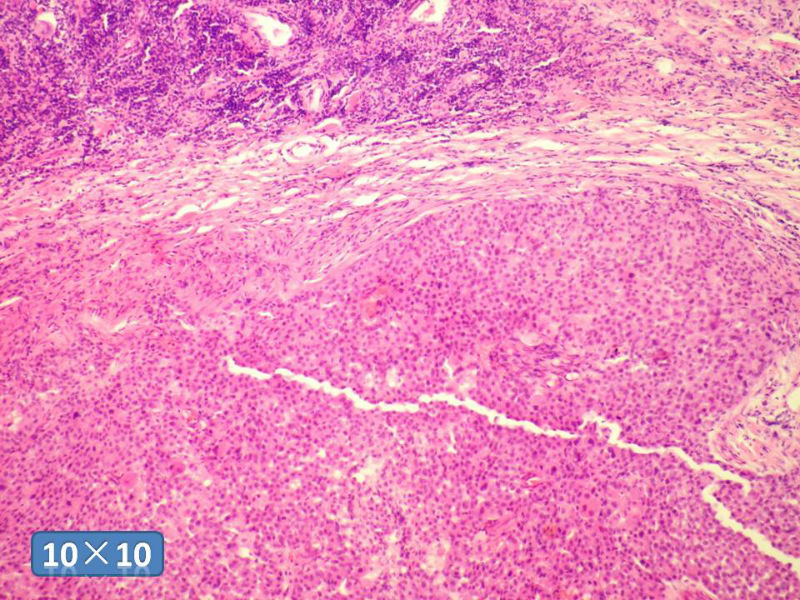

女性,50岁,乳腺肿物,冰冻切片(图1-25)

HE